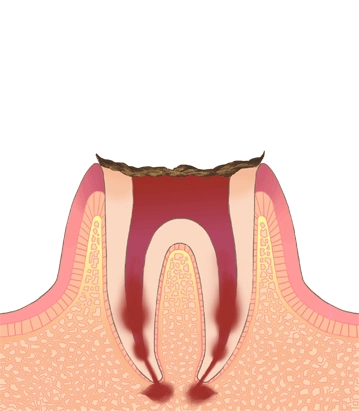

C4

最重度の虫歯

歯全体がむし歯に侵され、歯根だけが残ります。神経が死んで、歯根に膿が溜まります。